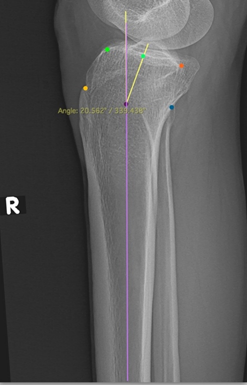

Role of Femoral Anatomical Mechanical Angle in Getting Alignment in Total Knee Arthroplasty

Siddhart Yadav , Shreyans Ghorawat , K P Chiranjeevi , Akash Singh Jadon , Sameer Pandey

Association of Posterior Tibial Slope and Metaphysio-Diaphyseal Angle with Radiographic Severity of Knee Osteoarthritis in the Indian Population

Rutvik Jain , Man Mohan Sharma , Pragyesh Jain